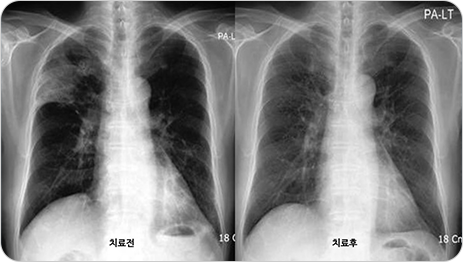

흉부 X-ray 촬영

침윤의 여부와 특징, 병변의 위치 및 침범 정도를 확인할 수 있습니다.

일부에서는 흉부 X선이 정상으로 보일 수도 있으며, 이 경우는 흉부전산화단층촬영(CT)으로 확인할 수 있습니다.